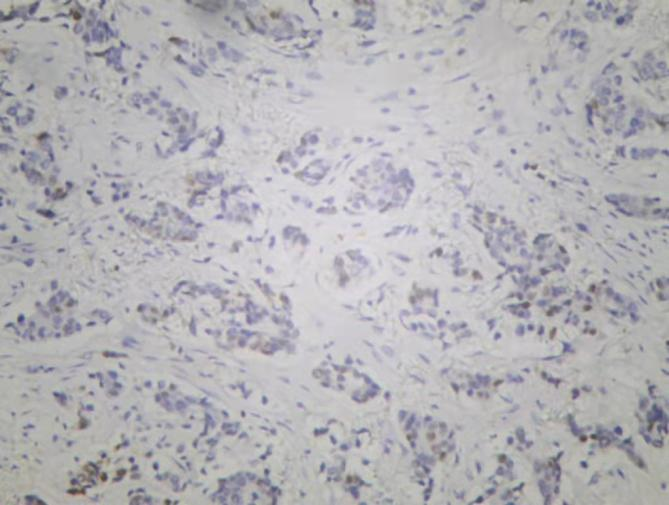

图3. 免疫组化Cerb-B2

图6. 免疫组化Ki-67